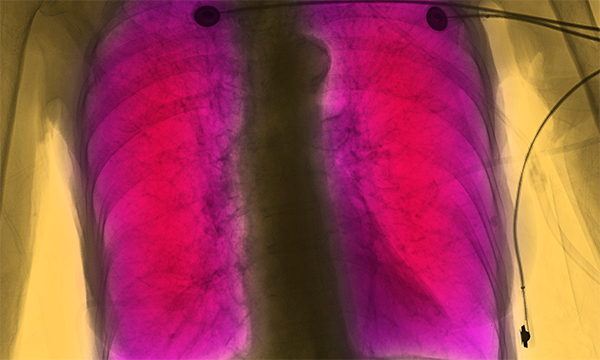

This is a summary of the peer-reviewed article: Abdominal X-rays in children: indications, proced